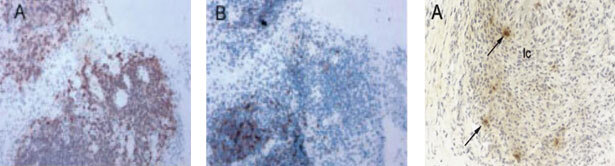

Как указывалось выше, принципиально единообразные патоморфологические изменения при системной прогрессирующей дезорганизации рыхлой волокнистой соединительной ткани свойственны всем нозологическим формам ИВРС. Это же касается и лимфоидного неогенеза. В качестве иллюстрации сказанного приводим рис. 7, где представлены фолликулоподобная структура в синовиальной оболочке при РА слева и фолликулоподобная структура в дерме и в мышечной ткани при СКВ. Видно, что морфологическая организация этих структур при РА и СКВ имеет черты определённого сходства. Важен тот факт, что процент мононуклеаров и нейтрофилов, подвергшихся апоптозу и находящихся в фолликулоподобных структурах при СКВ статистически значимо превышал аналогичные показатели в контрольной группе и коррелировал со степенью тяжести клинического течения СКВ [24].

Рис. 7. Слева фолликулоподобная структура с центром размножения (стрелка) в синовиальной оболочке при РА (Х 50), по материалам [173]. Справа фолликулоподобные структуры в дерме и в мышечной ткани при системной красной волчанке, Х100, по материалам [24]